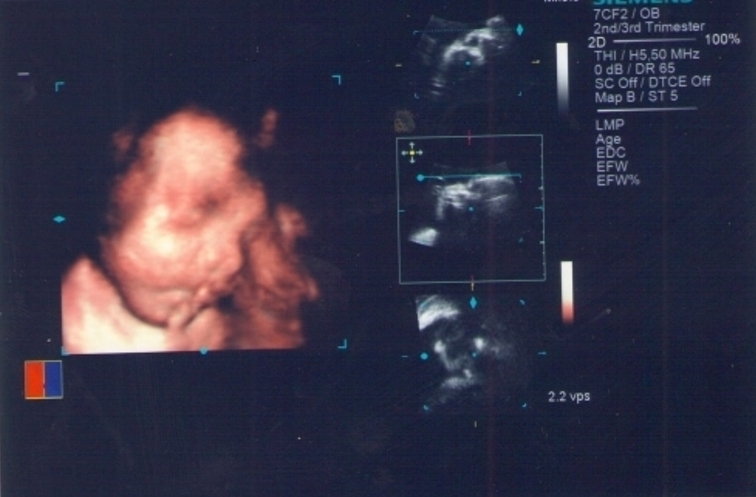

3D ultrazvuk – nejlepší filmový trhák v těhotenství aneb Naše první video

3D ultrazvuk